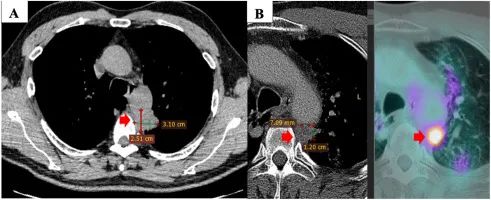

2019 年 5 月,一名 60 歲男性患者,無吸煙史,有咳嗽、背痛和疲勞癥狀,被診斷為非小細胞肺癌癌癥。CT 顯示原發(fā)性腫瘤位于左上葉 31×1 mm,侵犯主動脈周圍縱隔組織??v隔內(nèi)出現(xiàn)數(shù)個淋巴結(jié),最大尺寸為 15×5 mm,右肺上葉有 7 個淋巴結(jié)顯示,大小分別為 4 mm 和 2 mm。CT 引導(dǎo)下的結(jié)節(jié)和腺癌經(jīng)皮活檢通過組織病理學(xué)檢查(PHE)得到證實,病理分期為 T1N125M55a(IV 期)。腫瘤標志物 CA199 輕微升高,CA 和 CEA 之間的邊界正常。分子分析顯示 EGFR 沒有突變。由于病變較大,無法進行手術(shù)。

注:首次診斷時原發(fā)腫瘤的 CT 掃描檢查(A)。一線治療后原發(fā)腫瘤的 PET / CT 掃描檢查(3 個周期卡鉑 650mg(AUC5)加紫杉醇 300mg(175mg / m)2)與第三周期的放射治療聯(lián)合)(B)。

從 2019 年 6 月到 2019 年 12 月,患者接受了三個周期的聯(lián)合放療,其中卡鉑 650mg(AUC5)和紫杉醇 300mg(175mg/m2),第三個周期。癥狀已部分緩解,臨床和副臨床癥狀均有所改善?;颊叩恼娮影l(fā)射斷層掃描(PET)/CT 掃描顯示原發(fā)腫瘤的大小縮?。?/span>12×7 mm),腫瘤標志物值于 2019 年 12 月恢復(fù)正常。